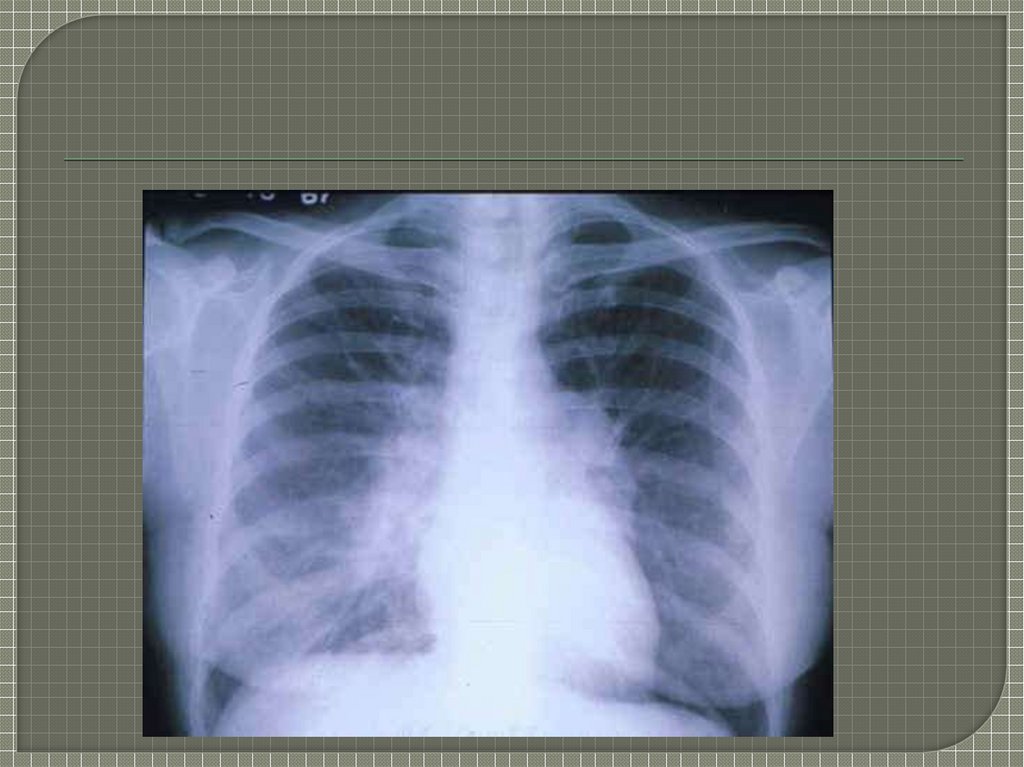

13. Rg Диагностика

-усиление и деформация легочного

рисунка

-тяжистость теней

-сетчатый и ячеистый рисунок

-уплощение плевры

-уменьшение подвижности диафрагмы.